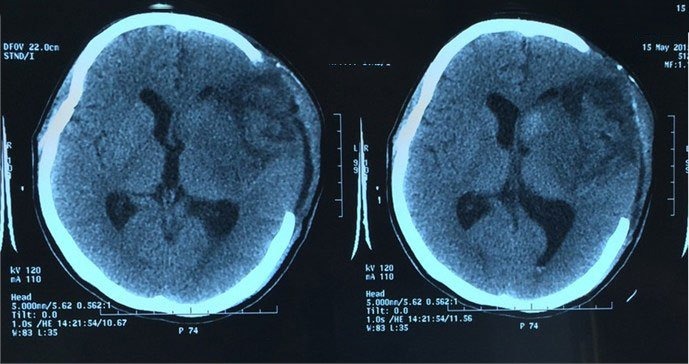

Bệnh phù não hay còn được gọi là tăng áp lực nội sọ là bệnh lý nguy hiểm đe dọa đến tính mạng người bệnh. Trong bài viết này hãy cùng tìm hiểu liệu bệnh nhân phù não có hồi phục được không và những yếu tố nào ảnh hưởng đến quá trình phục hồi.

Phù não là một tình trạng tăng áp lực nội sọ và có thể do nhiều nguyên nhân khác nhau gây ra: